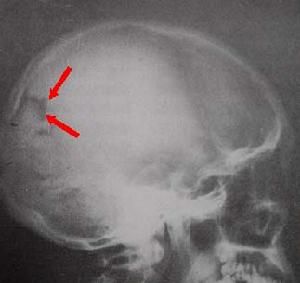

顱骨顱的側面在乳突的前上方可見外耳門,向內通外耳道。外耳門前上方的弓形骨梁稱顴弓。顴弓的內上方有一淺而大的窩,稱顳窩。在顳窩,額、頂、顳、蝶四骨會合處,常構成“H”形的縫,稱為翼點。此處骨質較薄,內有腦膜中動脈前支通過,若發生骨折時,容易損傷該動脈,引起顱內血腫。顳窩下方的窩稱顳下窩,顳下窩向內通翼齶窩。翼齶窩向下、向內側、向前、向後及向外分別與口腔、鼻腔、眶、顱腔及顳下窩相交通,是許多血管神經的通道。